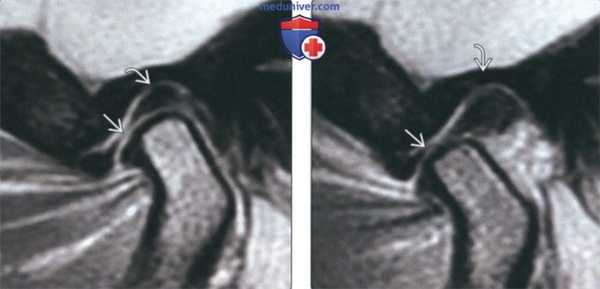

(Справа) В завершающей стадии закрывания рта до момента контакта зубов мыщелок находится в суставной ямке, а диск смещается вновь, обусловливая более мягкий щелчок закрытия рта. Задние связки диска растянуты и находятся в положении между 11 и 12 часами относительно мыщелка. (Слева) На косой сагиттальной PD МРТ (с закрытым ртом) визуализируется смещенный кпереди диск, задний пучок, которого находится на 10 часах относительно мыщелка. На более медиальном срезе диск занял нормальное положение. Следовательно, речь идет о частичном смещении диска.

(Справа) На косой сагиттальной PD МРТ (с открытым ртом) визуализируется промежуточная зона между мыщелком и гребнем суставного возвышения. В этом случае можно сделать заключение о частичном переднем смещении диска с редукцией. (Слева) На косом сагиттальном изображении центральных отделов ВНЧС с открытым ртом визуализируется вправившийся диск в этой зоне. При закрытом рте (изображения не продемонстрированы) диск был смещен кпереди.

(Справа) На косом сагиттальном изображении у этого же пациента (медиальнее по отношению к предыдущему срезу) визуализируется частично вправившийся диск. Задний пучок диска находится между мыщелком и суставным возвышением. Заключение: переднее смещение с частичной редукцией.

(Слева) На косой сагиттальной МРТ наружных отделов ВНЧС с за крытым ртом визуализируется задний пучокгя частично смещенный напротив 10 часов относительно мыщелка.

(Справа) На корональном изображении (под углом) у этого же пациента определяется боковое (наружное) смещение диска. Диск с внутренней стороны ВНЧС не визуализируется, медиальная коллатеральная связка растянута. (Слева) На косой сагиттальной PD МРТ с открытым ртом у этого же пациента определяется редукция диска, промежуточная зона которого находится между мыщелком и суставным возвышением. Трансляция мыщелка лишь незначительно отклонена от нормы. Заключение: боковое смещение с редукцией.

(Справа) На косой сагиттальной PD МРТ медиальных отделов ВНЧС с закрытым ртом визуализируется уплощенный задний пучок диска, расположенный между 10 и 11 часами относительно мыщелка. Утолщенная задняя связка, прикрепляющая диск к височной кости, визуализируется на 12 часах. (Слева) На косом корональном срезе у этого же пациента определяется боковое смещение диска кнутри. В наружных отделах НВЧС диск не визуализируется. Удлинена наружная коллатеральная связка.

(Справа) На PD МРТ наружных отделов ВНЧС с открытым ртом у этого же пациента визуализируется промежуточная зона диска между мыщелком и суставным возвышением. Заключение: боковое (кнутри) смещение диска с редукцией. Обратите внимание на хорошо различимую заднюю связку диска, крепящую его к височной кости.